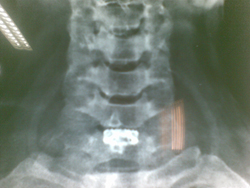

Cerv Spacer